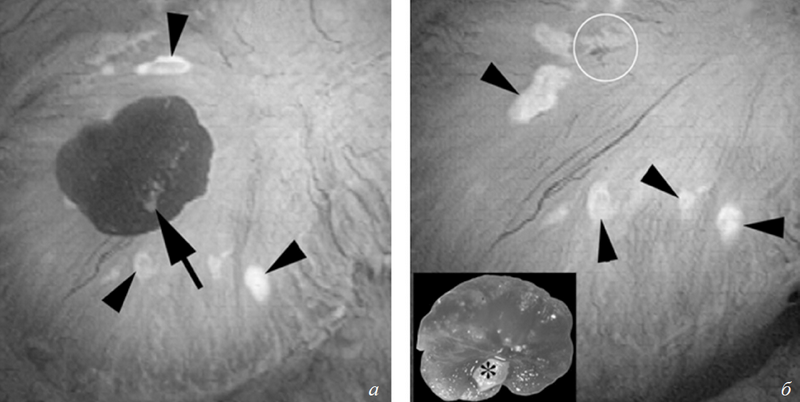

Во время эндоскопического удаления камня почки достаточно часто можно видеть камни, растущие на бляшках в области сосочков чашечек (рис. 1).

В 1937 г. Рэндалл [23] впервые продемонстрировал на трупах, а современная урология с помощью эндоскопической оптики подтвердила наличие «каменных» островков на сосочках, остающихся после удаления прикрепленных к ним камней, состоящих из гидроксиапатита (ГА). Посредством интраоперационных эндоскопических снимков [20] и микрокомпьютерной томографии можно воссоздать точную локализацию конкремента на бляшке, с которой он был удален, и показать, что большинство конкрементов действительно росли, прикрепляясь к бляшкам. Высокую вероятность «бляшечного» происхождения также имеют и камни свободно лежащие в полостной системе почки [21].

На фоне всех пациентов с мочекаменной болезнью явно выделяется фенотип больных, у которых формирование кальцийоксалатных конкрементов происходит без каких-либо системных заболеваний, способных прямо влиять на их возникновение; такие больные определены в группу с идиопатическим кальцийоксалатным нефролитиазом [5, 6]. У большинства из них можно проследить семейный и/или генетический характер наследования идиопатической гиперкальциурии. При этом кальцийоксалатные конкременты у этой группы пациентов образуются в основном на бляшках (см. рис. 1).

Рис. 1. Прикрепленные к бляшкам Рэндалла конкременты у идиопатических кальцийоксалатных (CaOx) камнеобразователей: а) эндоскопический вид камня CaOx, прикрепленного к верхушке почечного сосочка (на снимке отмечено стрелкой). Бляшки Рэндалла вокруг прикрепленных конкрементов (треугольники); б ) сосочек после удаления камня. На вставке видна папиллярная поверхность того же камня. Небольшой участок белесоватого материала на камне — гидроксиапатит, при этом сам камень на сто процентов кальцийоксалатный (отмечено звездочкой)